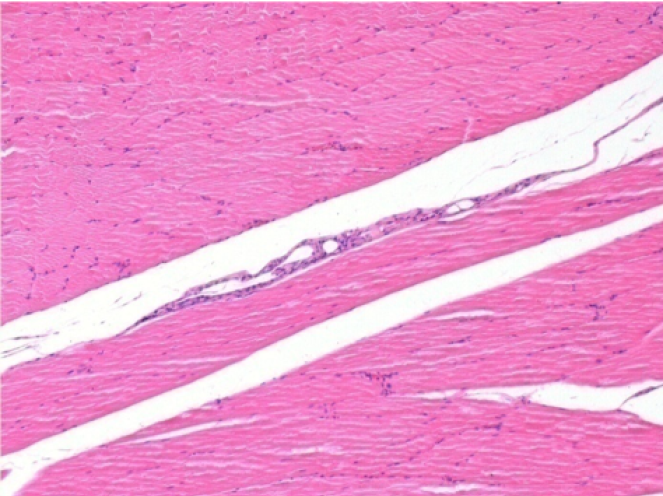

L:Pretibial-No treatment

R:Pretibial-After 0.1 ml NaCl 0.9% IM